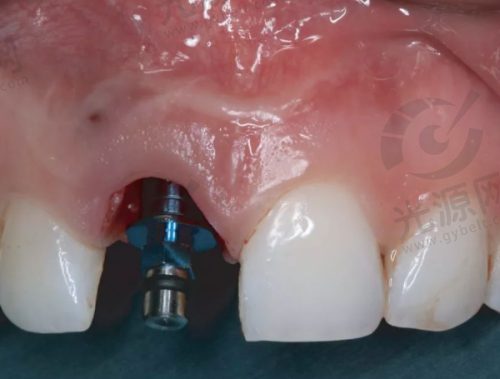

2. 种植牙:依据品牌与材料选择,价格从4599元 - 17000元都有。